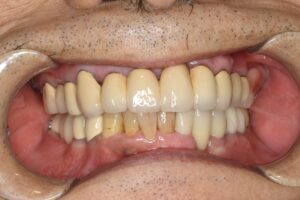

ケース2:上下に多くの問題があった70代後半男性

この方は虫歯や歯周病で残存歯が少なく、グラグラの歯が多い状態でした。最初は保険のクラスプ義歯を入れていたものの安定せず、硬いものを噛めないため外していることが多かったそうです。外見を重視してナイロン義歯を試されましたが、期待したような咬合回復は得られず、全体の再治療を希望して来院されました。

まず全顎の虫歯と歯周病の治療を行い、上顎は残存歯すべてに内冠をかぶせて連結し、全体を支えるテレスコープ義歯を製作しました。装着後は「入れ歯」というよりは取り外し可能な長いブリッジの感覚で、違和感がほとんどないとのことです。

このケースは「残った歯をチーム化して守る」発想が有効であった例です。